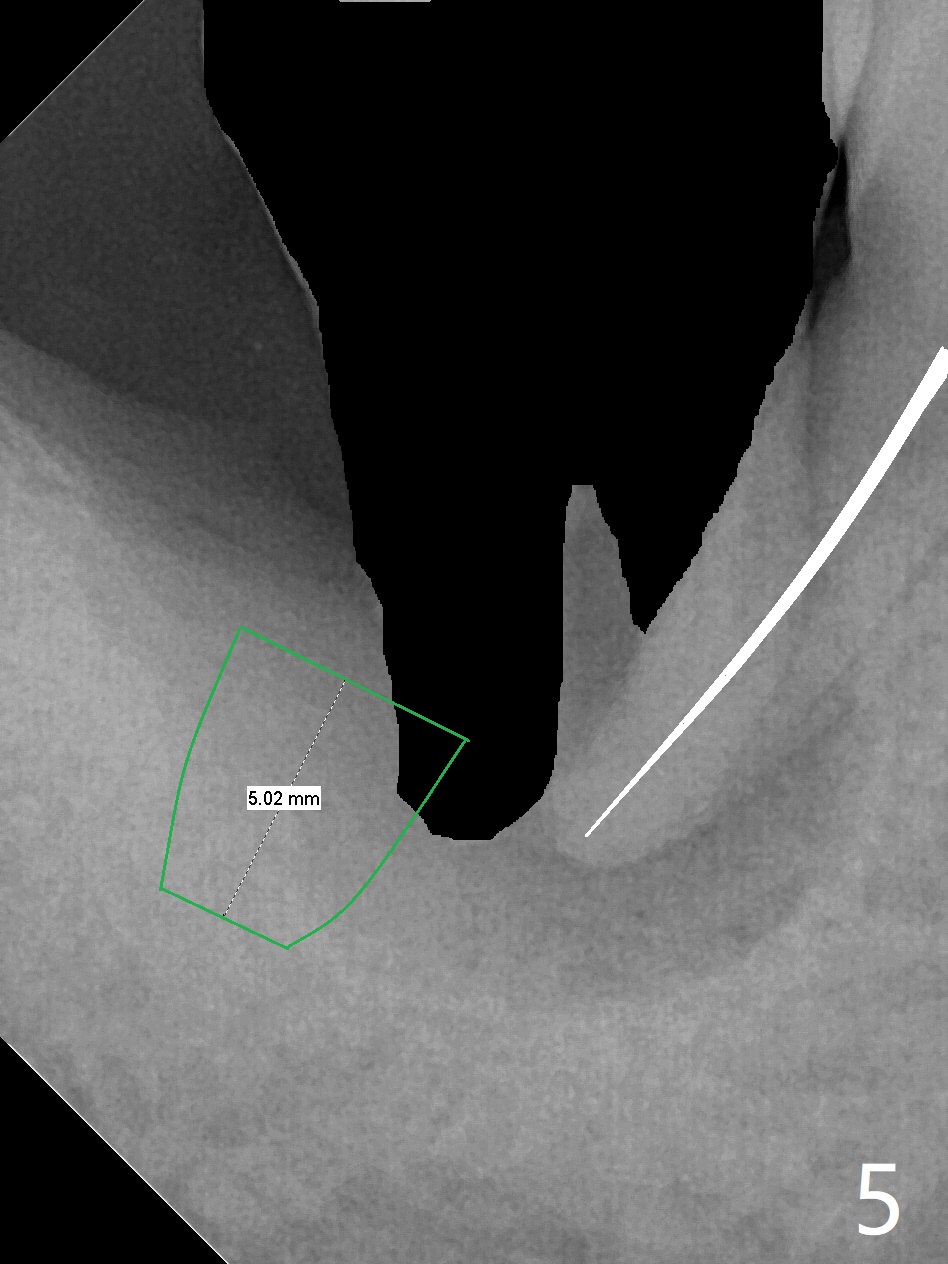

A 47-year-old man, a possible bruxer (Fig.1), is concerned about the mobile 2nd molar and lower central incisor (Fig.2,3). To prevent periimplantitis, a 2 mm 1-piece implant and a short one (5x5 mm) will be placed subcrestal at these sites, respectively (Fig.4,5). Sticky bone is a must. Pulpal test will determine whether RCT is required for #30 (Fig.5 curved white line). In fact the tooth #30 is tested to be vital. Onlay graft is an option for #31 (Fig.6 red rectangle). There is history of #32 extraction. The severely periodontally affected tooth #25 (Fig.7 *) has narrow mesiodistal space (Fig.8). It is the best treated with extraction with bone graft and self drifting.